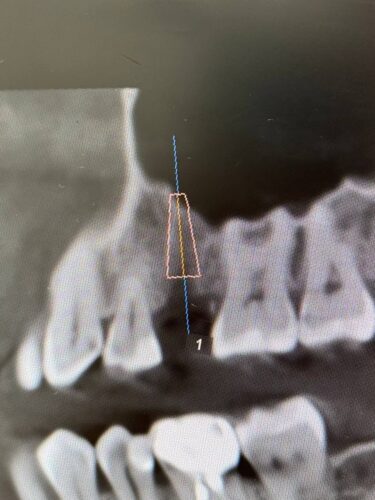

Установка импланта